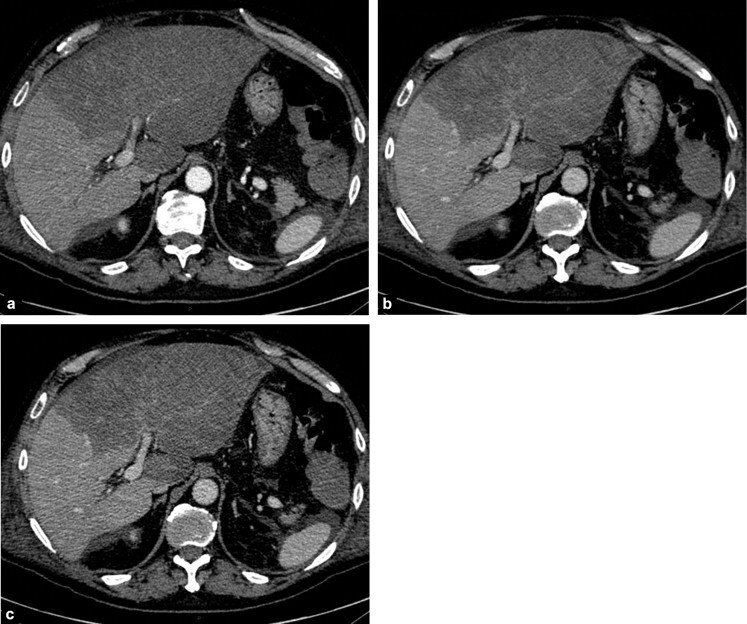

Na TC a avaliação é feita na fase pré-contraste. Avalia-se objetivamente através do valor absoluto e comparativo do ROI (diferença >5 entre fígado e baço) e subjetivamente através da visualização dos vasos.

Verdadeiro.

V ou F?

A lesão hipoatenuante próxima ao hilo hepático corresponde a um nódulo a ser esclarecido.

A

Falso.

A lesão hipoatenuante próxima ao hilo hepático corresponde a área poupada de esteatose.